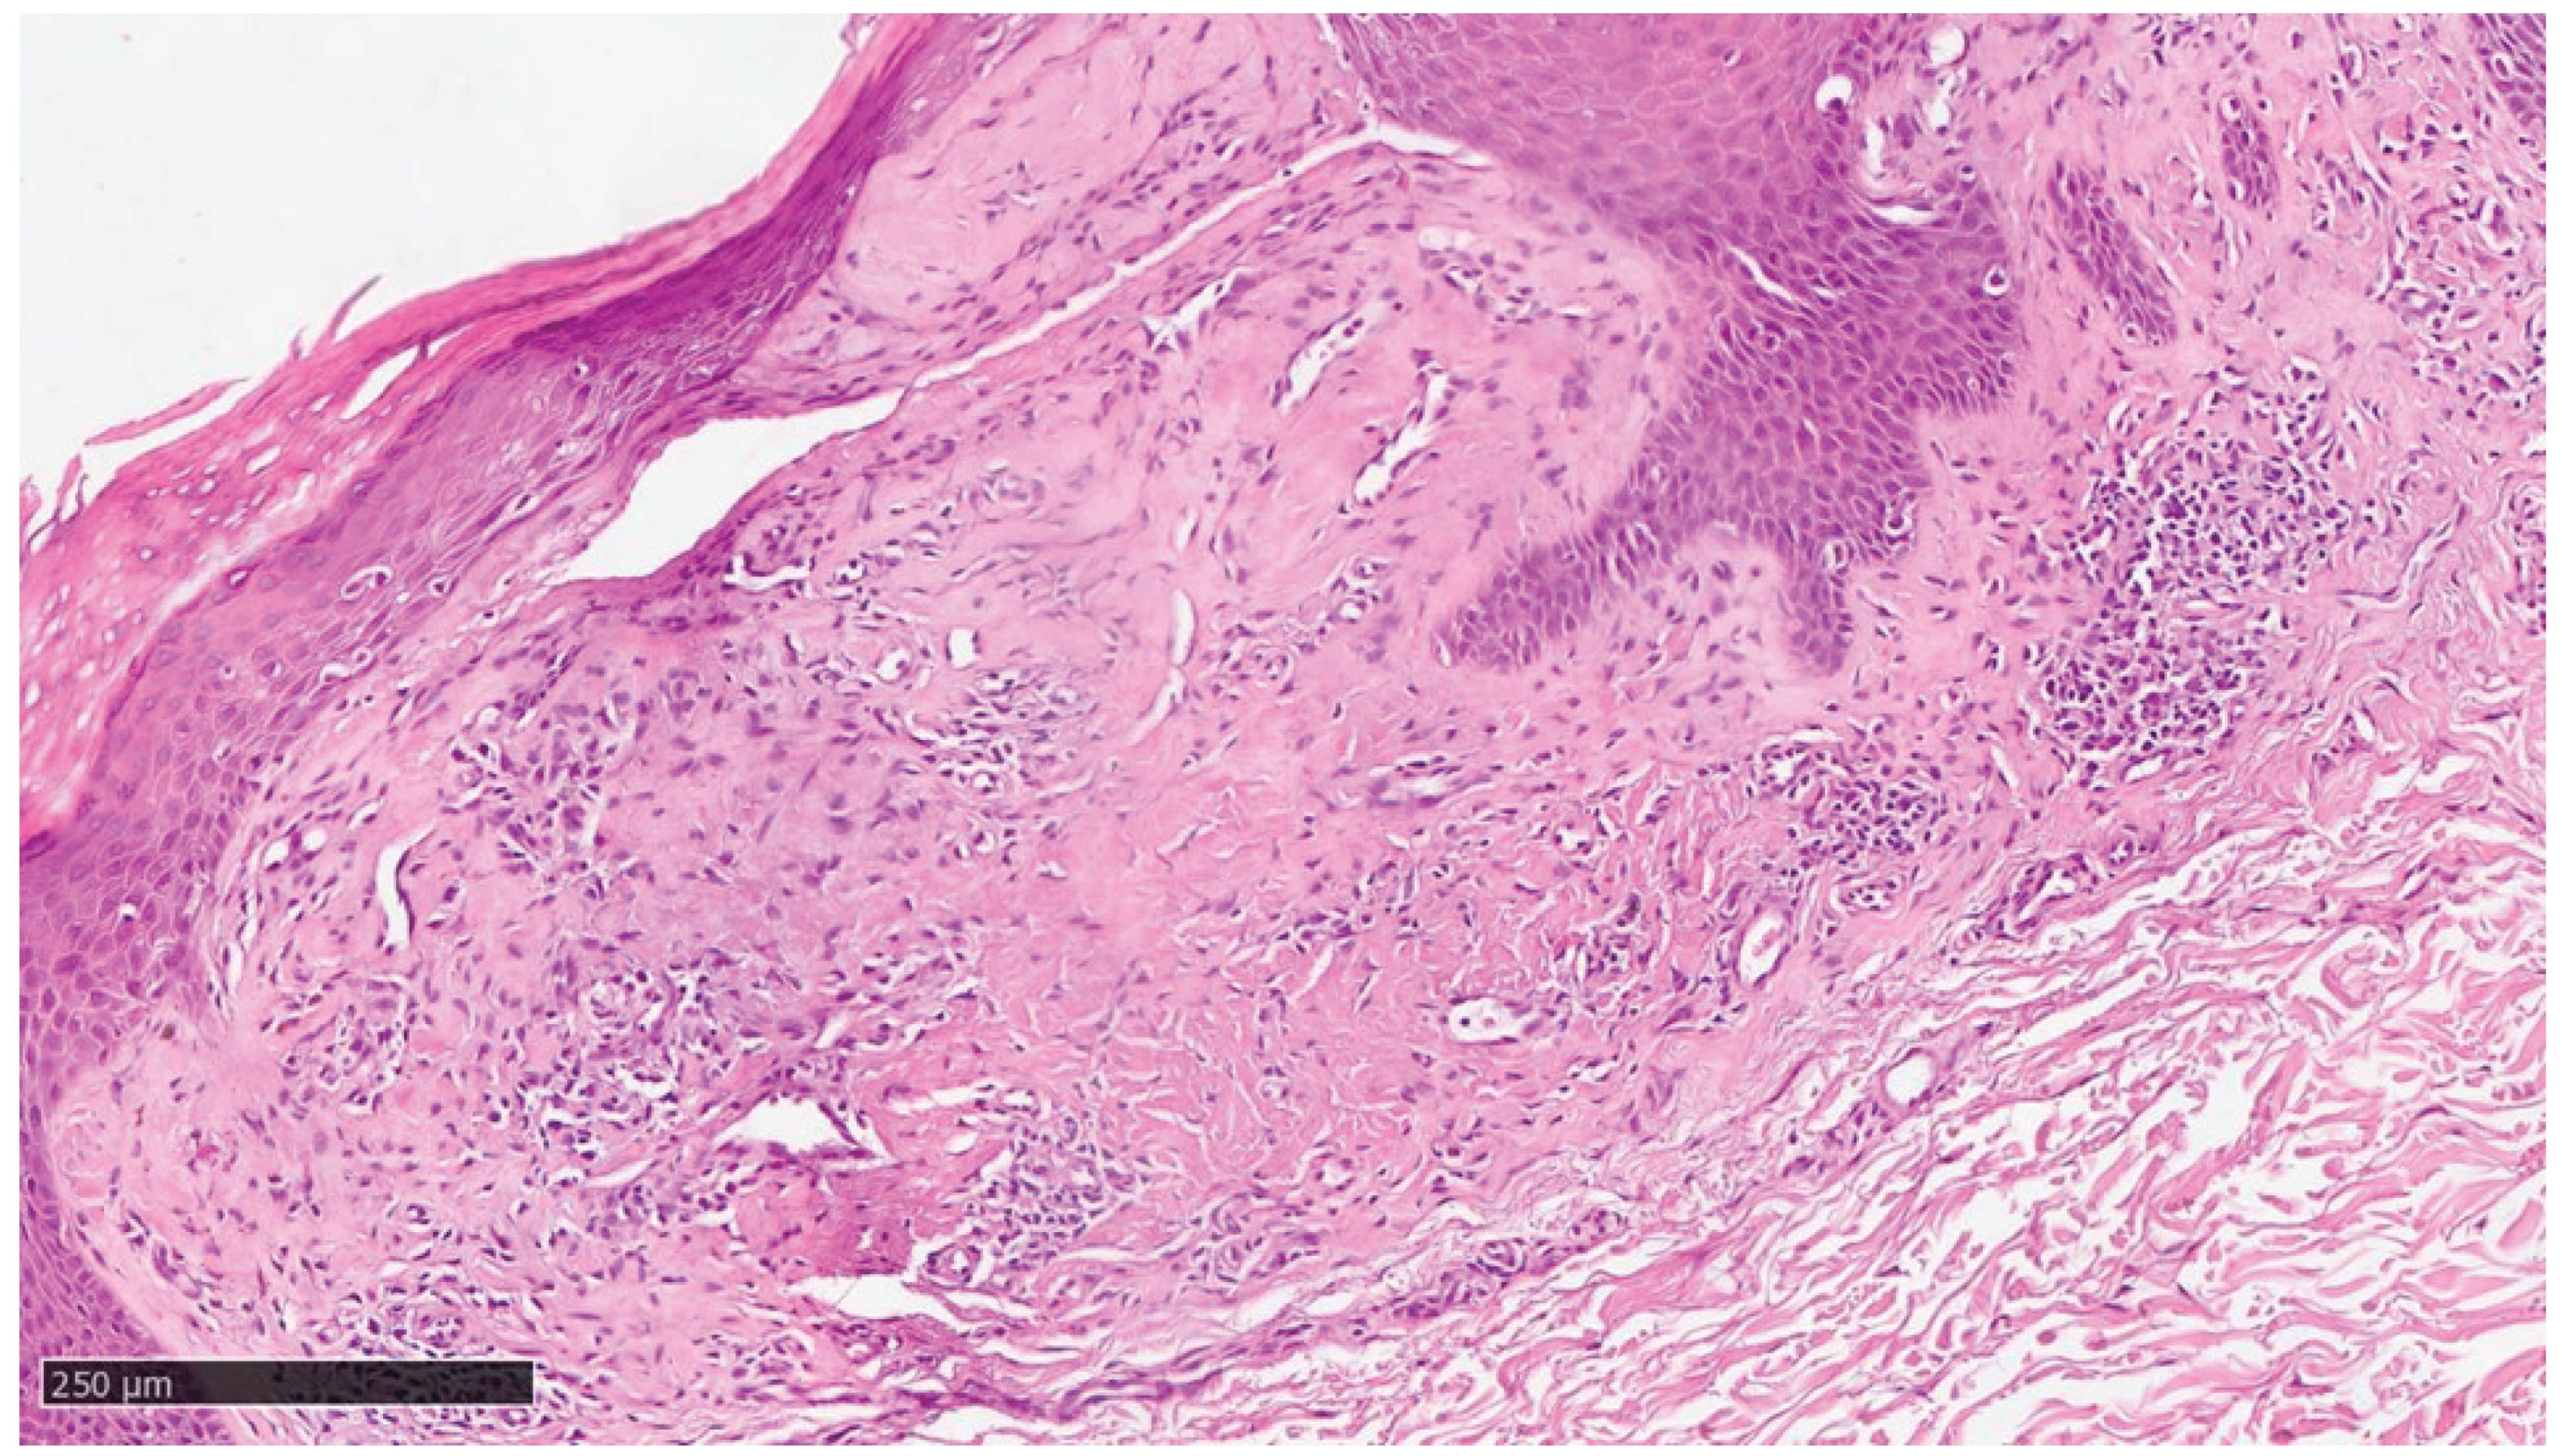

At our clinic for a diagnosis of certainty of LA, an incisional biopsy was performed at typical infiltrated plaques on the lower limbs. The histopathological investigations reported typical LA findings such as deposition of amyloid material at the papillary dermis, beneath to dermo-epidermal junction; there were also some areas with incontinence of melanic pigment and diffuse inflammatory infiltrate at the middle and superficial dermis. The epidermis was not interested by this infiltration and acts as an innocent bystander with acanthosis, hyperkeratosis and elongation of the epidermal ridges (Figure 3 , Figure 4 and Figure 5).

Figure 4. Scanning magnification of the previous picture showing the amyloid deposition beneath the dermo-epidermal junction with the typical cleft (white spaces) and moderate lymphocytic infiltration in the middle dermis (Hematoxylin-Eosin, Original Magnification 10x).